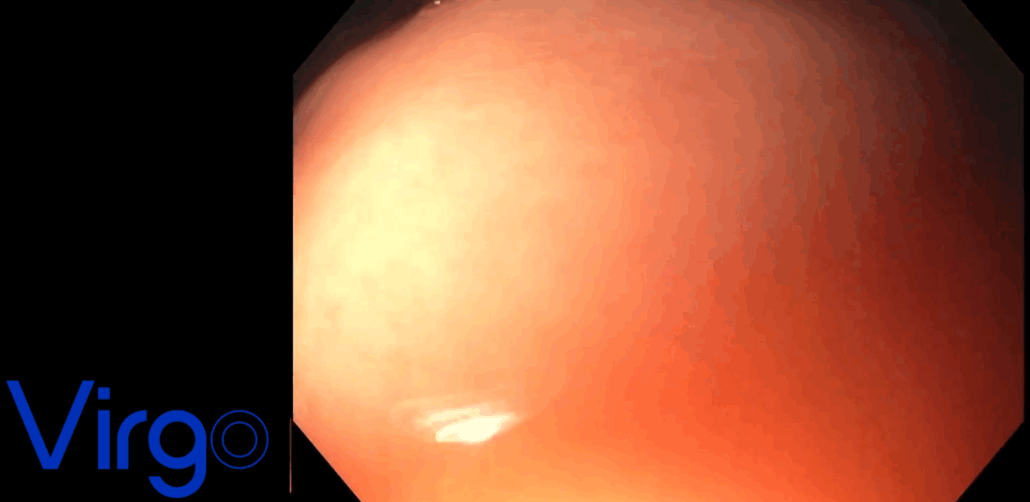

TIF 2.0 procedure snapshots

TIF 2.0® Procedure Overview

The TIF 2.0® (Transoral Incisionless Fundoplication) procedure is an advanced endoscopic treatment that reconstructs the gastroesophageal flap valve (GEFV)—targeting the root anatomical cause of GERD (Gastroesophageal Reflux Disease). By restoring the natural antireflux barrier, TIF 2.0 offers a physiological solution without the need for external incisions or dissection.

Using the EsophyX Z+® device, the procedure creates an approximately 3 cm, 270° esophagogastric fundoplication. This device employs proprietary tissue manipulation technology to place 20+ SerosaFuse® fasteners, distributing tension evenly across the wrap’s entire circumference under direct endoscopic visualization via a flexible endoscope positioned in the central lumen.

The result is a reproducible, standardized, omega-shaped GEFV that closely mimics the patient’s natural anatomy, even in patients with hiatal hernias.